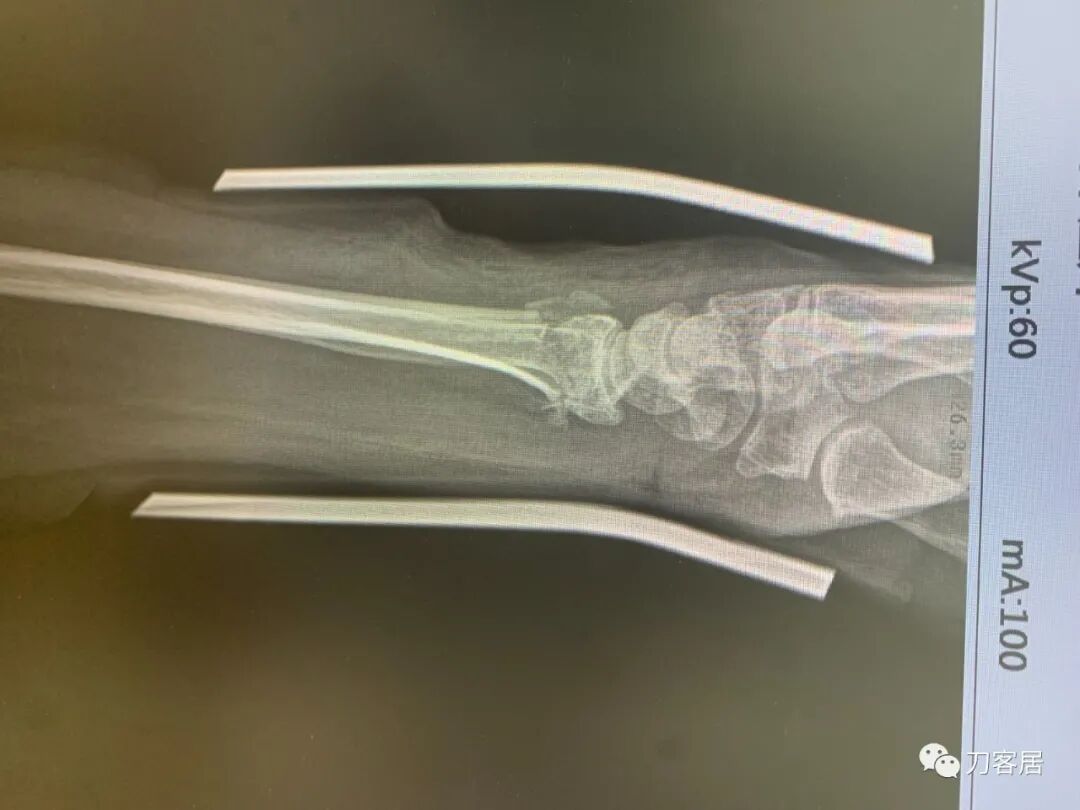

下面是这个6岁孩子,尺桡骨远端双骨折的术前及术后片子和外观照片。

1.  这是一个很简单的6岁儿童无移位的尺桡骨远端骨折。没有皮肤损伤,没有移位,没有骨折碎块儿。

2.  这个骨折处理起来也很简单,单纯的打石膏托或者中医的小夹板,或者正规的包括腕关节和肘关节的管型石膏外固定4周即可治愈该骨折。实在不行,如果这个孩子比较听话,不太调皮的话,用一本书,一个三角巾悬吊固定4周,都可以治愈该骨折。但是给这个患者用外固定架做了手术,而且桡骨远端的几颗克氏针距离骨折线太近,其中一枚克氏针进入到骨折间隙内。从这个术中图片来看,术者的外固定手术技术也有待于进一步的提高。毕竟术者应该还很年轻。从X线片来看,前臂及手的尺侧有不透光影,应该还使用了外固定石膏绷带托,而且我猜测应该是高分子的石膏绷带托,这个是纯属猜测,不一定是对的,不过如何解释前臂尺侧的不透光影呢?如果真是用了石膏绷带外固定的话,那为啥要做手术呢?外固定架术后就不该再用石膏绷带托辅助了。